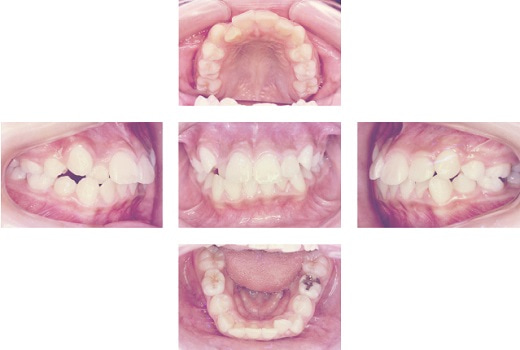

でこぼこが気になるという悩みから来院され、叢生を伴う上顎前突と診断。マルチブラケット装置を用いた治療を行い、2年3ヶ月で矯正治療が終わりました。

| 治療内容 | マルチブラケット装置 |

|---|---|

| 治療期間・回数 | 2年3ヶ月/27回 |

| 費用※自由診療となります。 | 1,083,500円(税込) |

| リスク・副作用 | ・装置が付くと装置に擦れて口内炎が出来やすくなる ・歯が動くときに痛みがでることがある ・装置が付くと歯みがきが難しくなるため虫歯や歯肉炎につながりやすい ・患者様に協力していただけないことがあると治療が進まない事がある ・治療後、保定装置(リテーナー)を指示通り入れないことや、その他の指導内容が守れない場合、後戻りする可能性があること ※上記の内容は個人差があり、全ての方に当てはまるものではございませんので参考としてご覧ください。 |